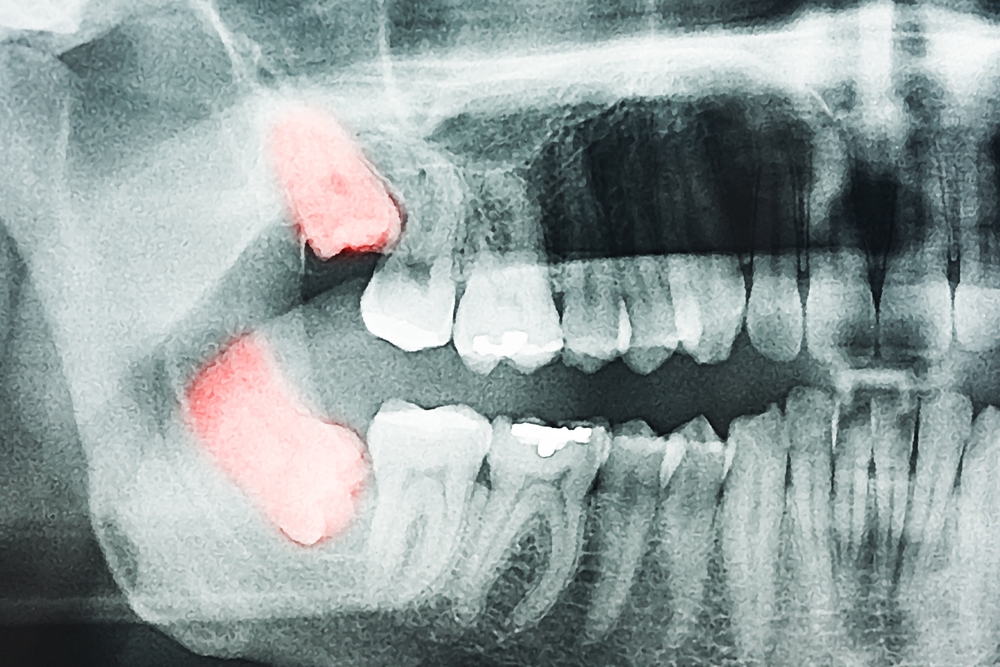

The best way to know if you have a wisdom tooth and where they are positioned is to have an x-ray. This will show if they are impacted or stuck under the gums and if they are likely to present any problems.

Your dentist will take an X-ray of your mouth to help determine whether the wisdom teeth should be removed and clarify their recommendations.

The best way to know if you have wisdom teeth and where they are positioned is to have an X-ray. This will show if they are impacted or stuck under the gums and if they are likely to present any problems.